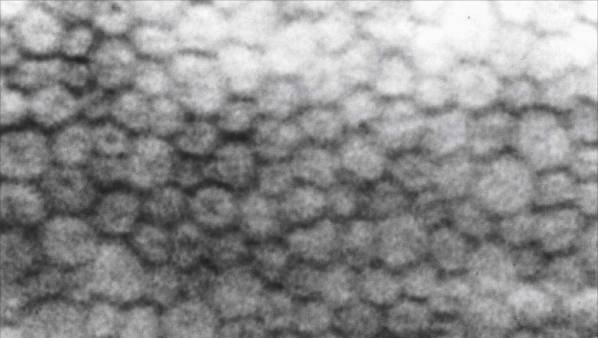

С использованием данной методики можно проанализировать различные характеристики поверхностного слоя роговицы:

- плотность клеточного контакта;

- различия в размерах соседних идентичных клеток;

- количество клеток правильной и неправильной формы;

- выявление темных участков, возникающих после воспалительных процессов или хирургических вмешательств.

Методика предоставляет возможность исследовать все эти параметры в живом организме. Это означает, что для проведения микроскопического анализа не требуется брать образец ткани.